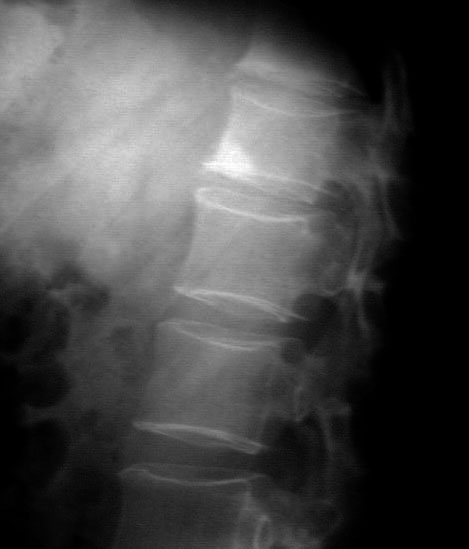

SIGNO DE LA ESQUINA BRILLANTE

Signo visible en la proyección lateral de columna, que consiste en el aumento de la densidad de una esquina del cuerpo vertebral, característico de la espondilitis anquilopoyética. Esta lesión representa la fase final de un proceso de erosión del cuerpo vertebral (lesión de Romanus), que ocurre en el margen anterosuperior o anteroinferior del mismo. Inicialmente solo es visible en RM como un edema óseo, hiperintenso en T2 y STIR. Más tarde aparece la esclerosis ósea visible en la radiografía, correspondiente a una degeneración grasa postinflamatoria del hueso esponjoso. En esta etapa, la lesión es hiperintensa en secuencias T1 de RM.